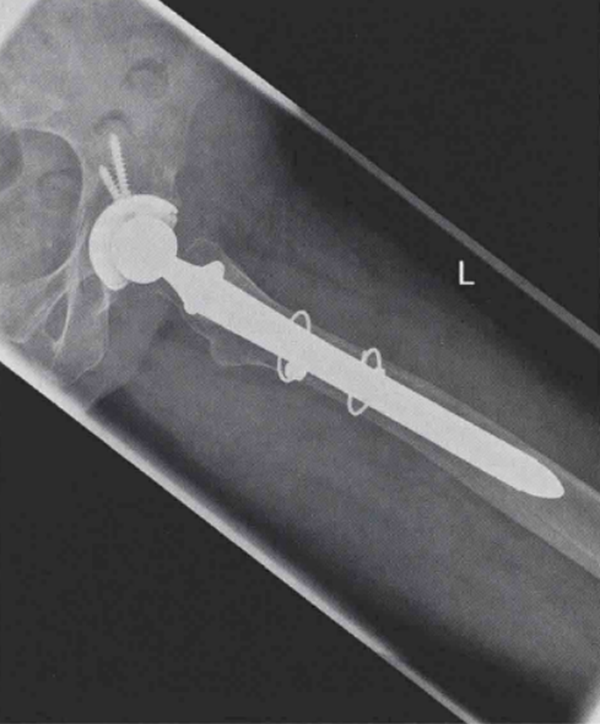

术后,患者可在完全负重下活动。术后X线片显示效果满意(图4和图5)。患者持续恢复良好。3个月随访中,患者完全无不适症状。

图4 左髋翻修术后正位X线片,使用远端固定型柄跨过骨折端,达到良好的远端固定效果1

图5 左髋翻修术后侧位X线片,使用远端固定型柄跨过骨折端,达到良好的远端固定效果2